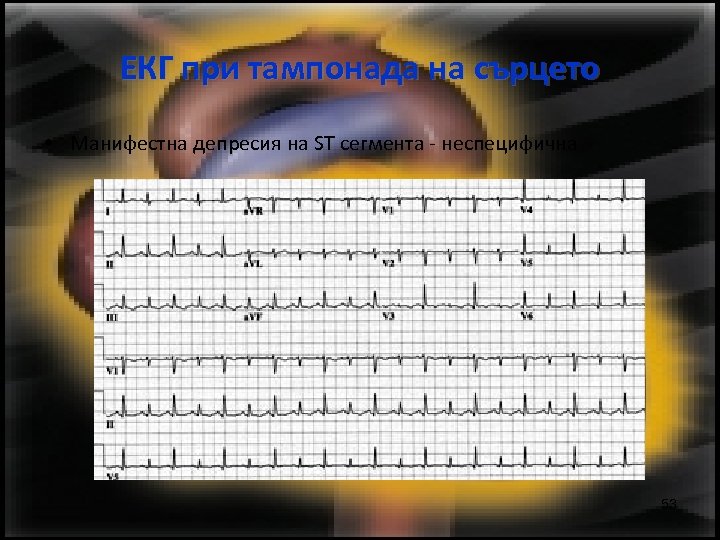

ЕКГ при тампонада на сърцето • Манифестна депресия на ST сегмента - неспецифична 53